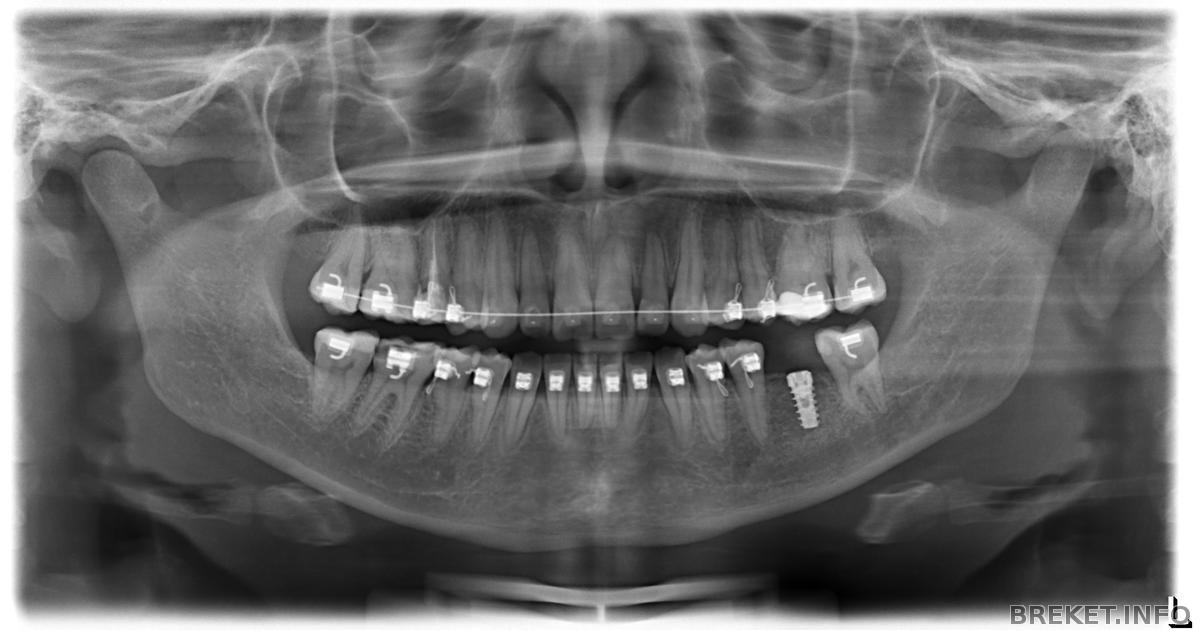

имплантация

сегодня у меня появился новый титановый зуб!!!!! ура я сделала это . Операция по вживлению имплантанта была быстрой и безболезненной.